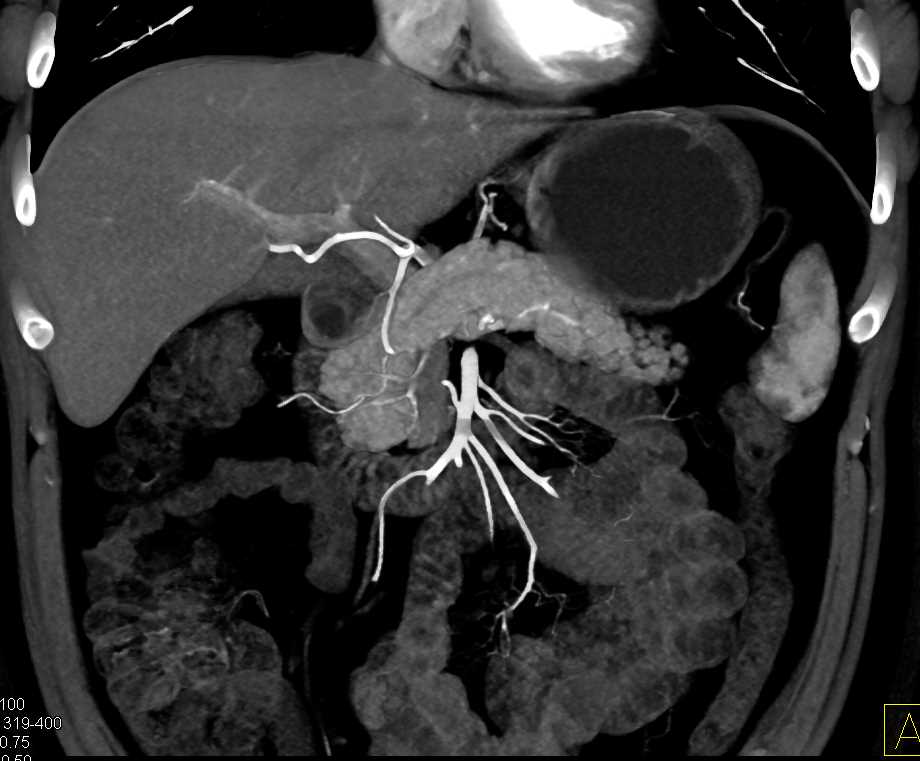

Neuroendocrine Tumor Body of Pancreas